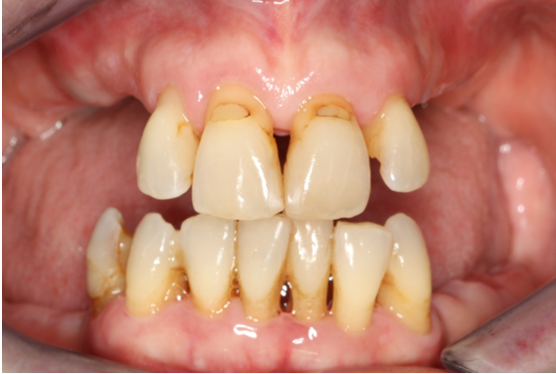

Ασθενής ετών 50 προσήλθε στο ιατρείο με κύρια ενόχληση την αιμορραγία των ούλων και τη μετακίνηση των δοντιών. Οι περιοδοντικοί ιστοί ήταν ρόδινοι και εντοπισμένα ερυθροί, ενώ οι μεσοδόντιες θηλές διογκωμένες. Πολλά δόντια εμφάνιζαν υφιζήσεις, ενώ χαρακτηριστική ήταν η υπερέκφυση και απόκλιση του πλαγίου τομέα άνω αριστερά.

Παράλληλα με την περιοδοντική θεραπεία έγινε η αφαίρεση των παλαιών προσθετικών εργασιών και τοποθέτηση νέων μεταβατικών (προσωρινών) αποκαταστάσεων. Μετά τη μη χειρουργική θεραπεία παρατηρείται απουσία φλεγμονής.

ΑΡΧΙΚΗ ΚΛΙΝΙΚΗ ΕΙΚΟΝΑ

ΤΕΛΙΚΗ ΚΑΤΑΣΤΑΣΗ